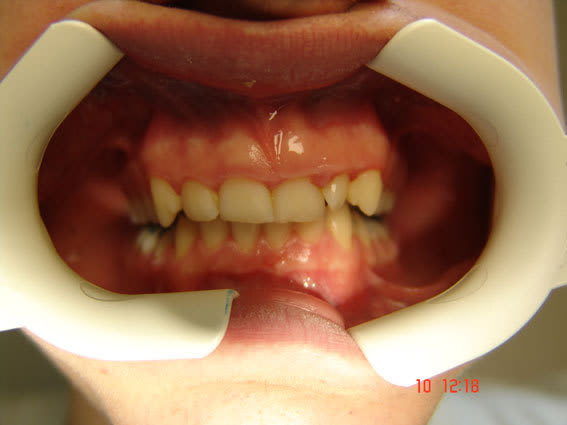

Pour la première photo, je lui ai demandé de ne pas fermer complètement de manière à mettre en évidence la déviation du point interincisif inférieur, à noter que les freins ne sont pas alignés non plus.

Au total: supraclusion incisive, déviation point interincisif inf vers la droite, décalage entre les bords libres des incisives / canines et le plan occlusal des molaires prémolaires, déglutition dents serrées. Pas de caries. Paro+/-. Hypotonie droite (cfr épaules).

sur la premiere photo il semble que on a un quasi articulé inversé au niveau de la 45, la 11 est plus usée que la 21 mais la 13 est quasi intacte (trés longue mais normal à 14 ans)et donc je dirais qu'il mastique à droite et seulement à droite.